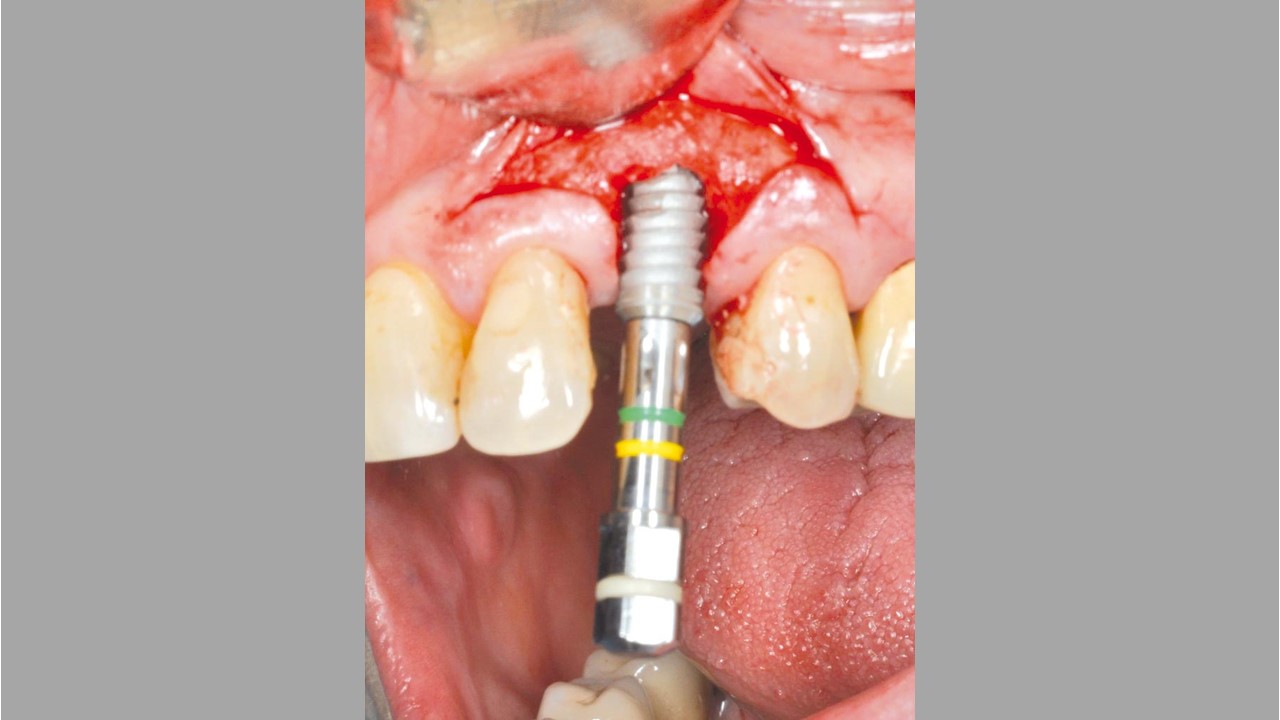

botiss cerabone® & Jason® membrane for GBR - Clinical case by Dr. S. Kovalevsky

Implant insertion in atrophic alveolar ridge